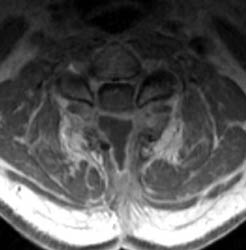

46 y.o.  male, initial complaint of progressed with myelopathy, difficulty walking, and imbalance. Underwent laminectomy C3 to C7, 2 months prior to these images. Worsening numbness and weakness brought patient to seek neurosurgical consultation again, prompting repeat imaging.

Sagittal T1 pre (A) and post contrast (B),  sagittal T2 (C) and Axial T1 post contrast (D) MRI images of the cervical spine demonstrating a large posterior fluid collection with an obvious sinus tract inferiorly and associated gas bubbles. This was proved to be a post-operative seroma and epidural scar (note the thick rind of enhancement) that was partially accounting for this patient's residual and worsening symptoms despite the initial decompressive surgery.